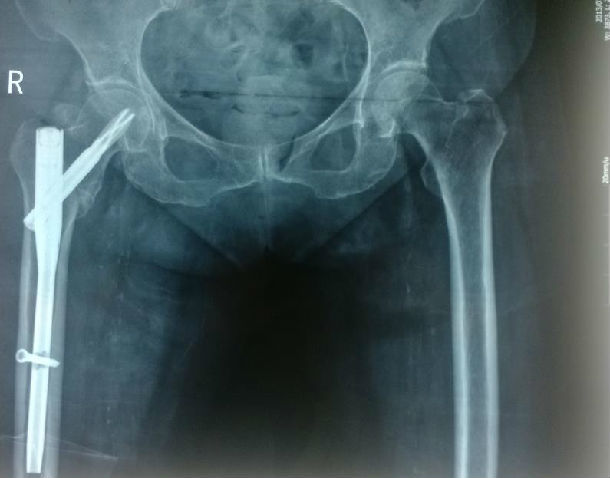

5、患者,女,65岁,意外摔倒致右髋疼痛、活动受限10天,入院诊断:右侧粗隆间骨折。给予行内固定手术治疗,术后情况恢复满意,术后X线片如下: